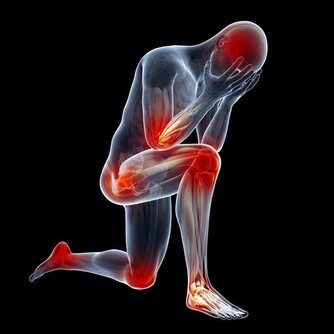

*****9、愛喝高度酒*****

小酌怡情,貪杯傷胃。酒精飲品在20°以上時,每小時飲用超過100ml,就可能會直接破壞胃黏膜屏障,引起充血、水腫、糜爛,甚至出血。飲酒時盡量選擇低度酒,且不要過度飲酒,避免急性傷胃。